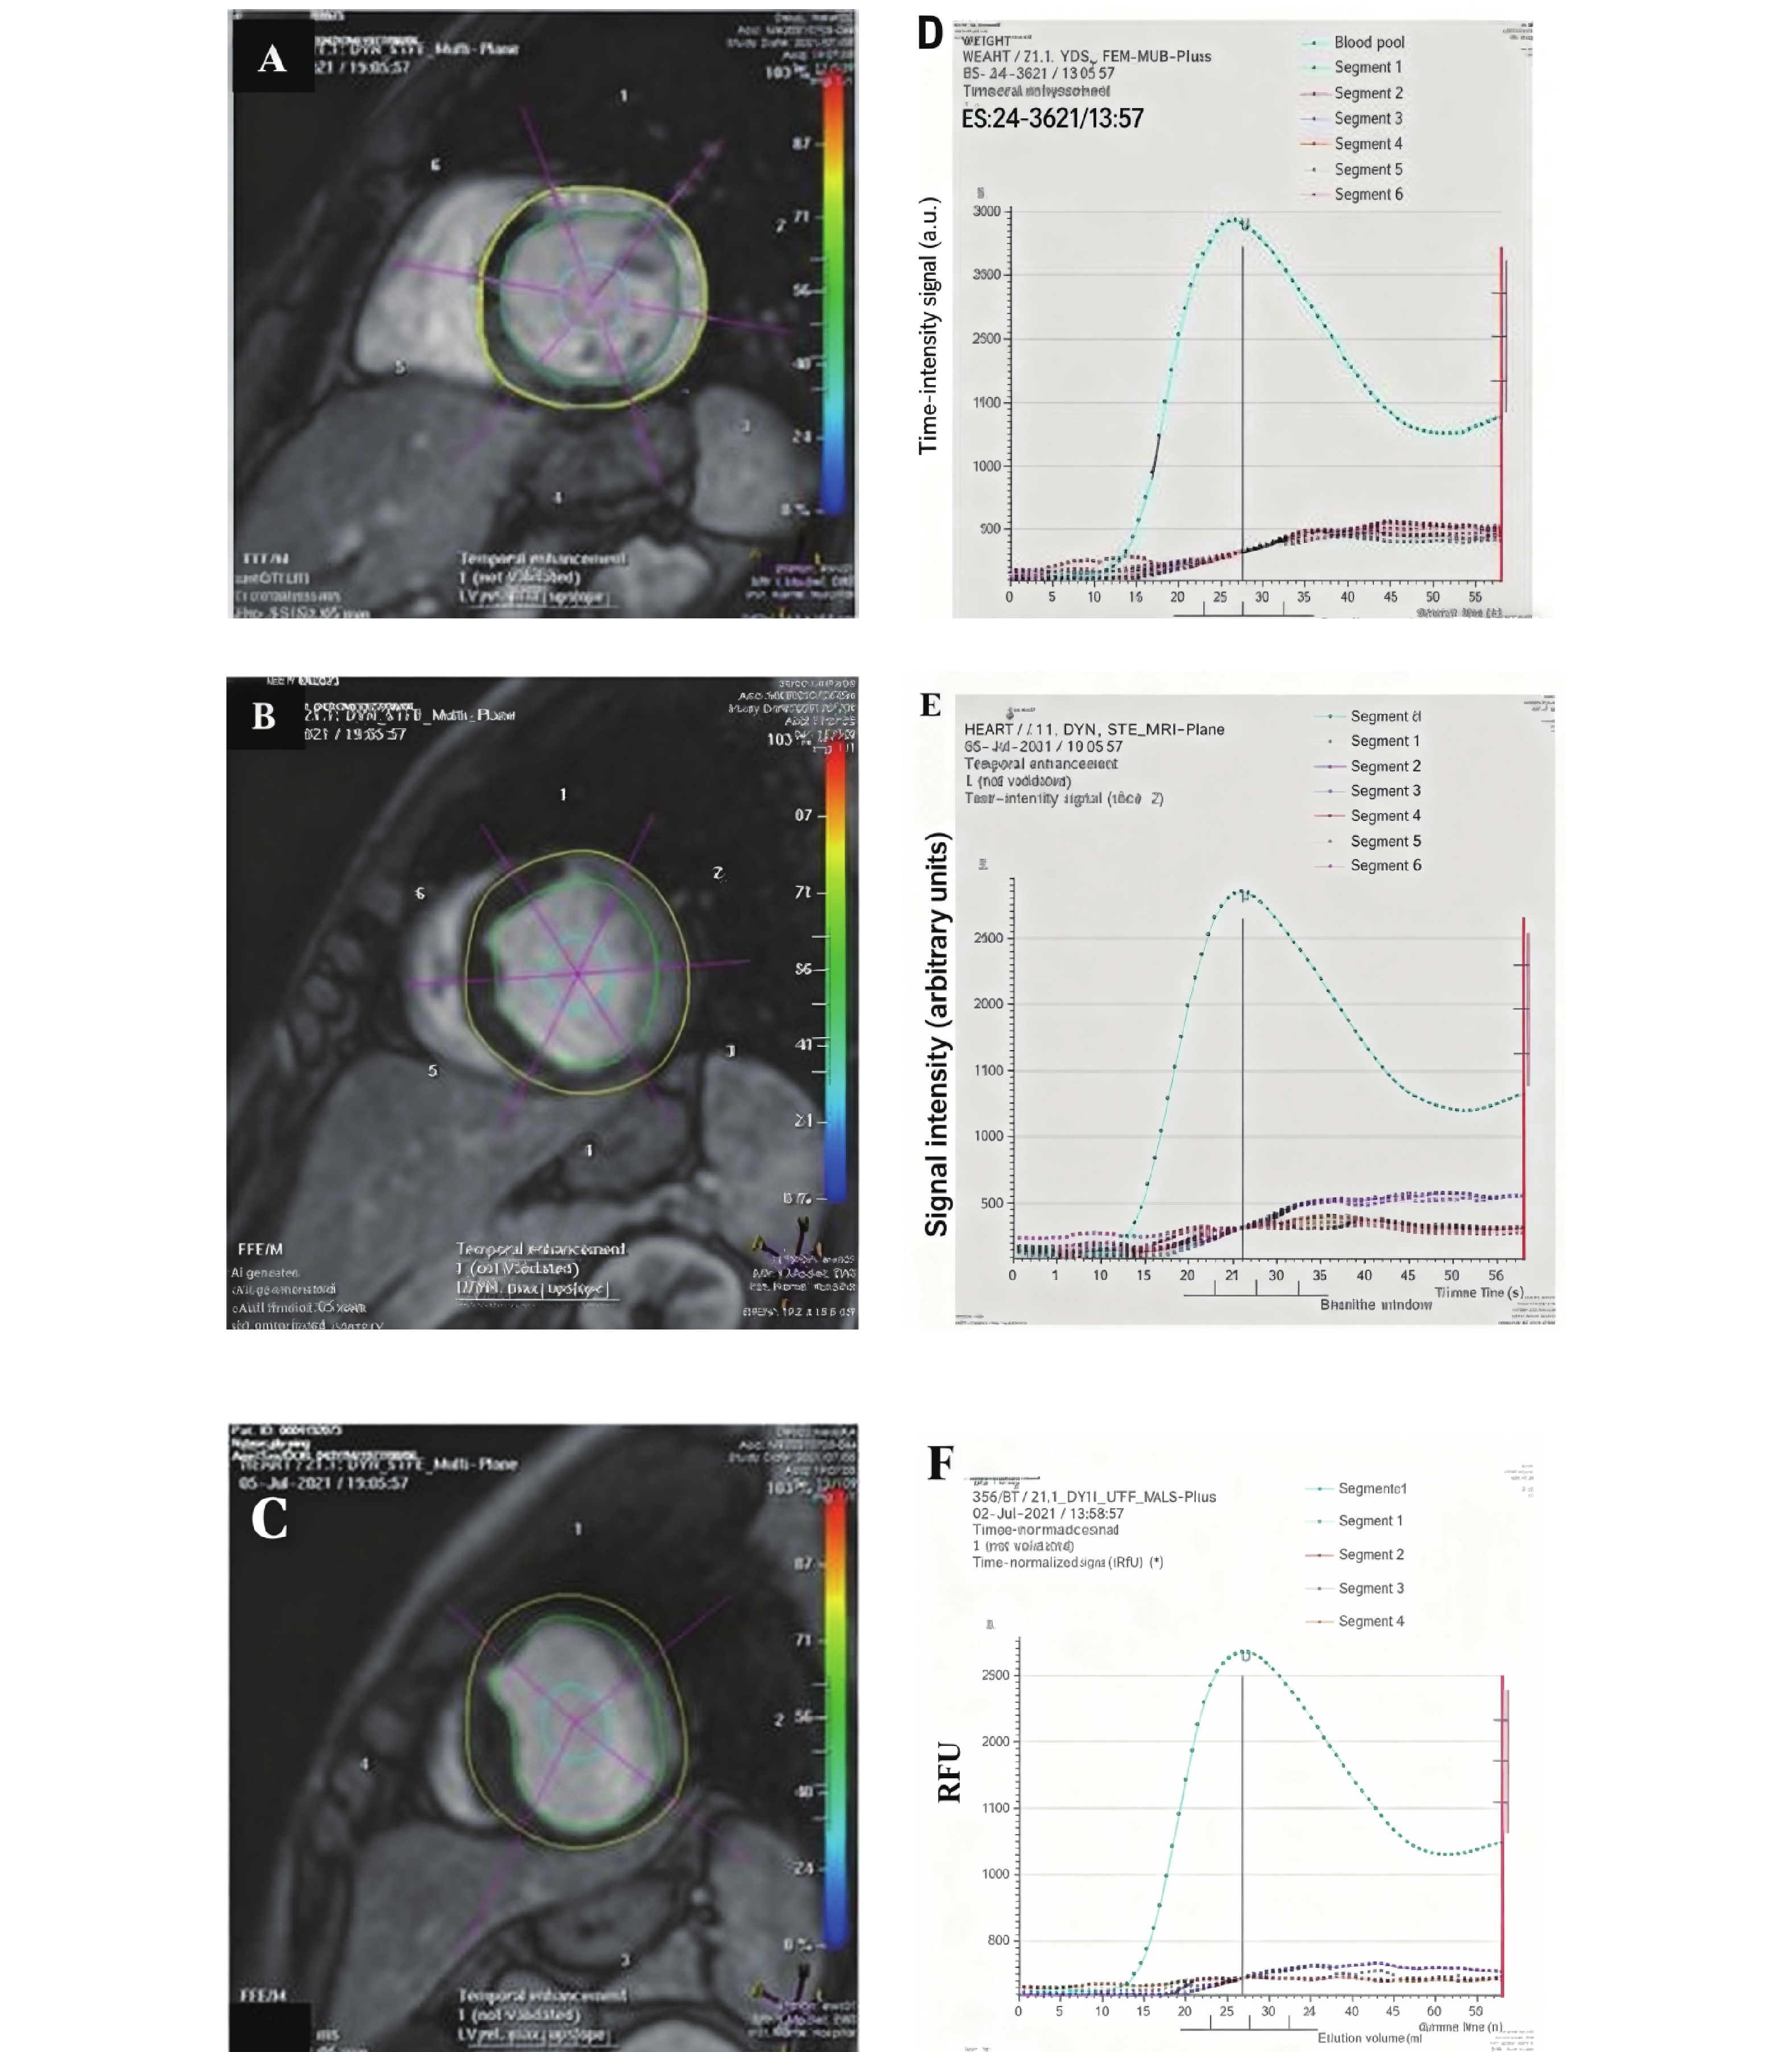

心肌超声造影心动图联合三维斑点追踪成像预测NSTEMI患者PCI术后主要心血管不良事件的风险

文婷, 曾令娇, 黄叶, 邱清勇, 朱玲玲

摘要(85) HTML(49) PDF (29)

摘要:

目的   探讨心肌超声造影心动图(myocardial contrast echocardiography,MCE)联合三维斑点追踪成像(three-dimensional speckle tracking imaging,3D-STI)对非ST段抬高型心肌梗死(non-ST-segment elevation myocardial infarction,NSTEMI)患者经皮冠状动脉介入治疗(percutaneous coronary intervention,PCI)术后主要心血管不良事件(major adverse cardiovascular events,MACEs)的预测作用。  方法   选取2022年5月至2024年3月中国人民解放军联勤保障部队第九二八医院254例NSTEMI患者,行PCI术,根据出院1年内MACEs发生情况分为MACEs组、无MACEs组,比较两组临床资料、常规超声心动图参数、MCE参数[平台期峰值强度(peak intensity,A)、灌注计分指数(perfusion score index,PSI)、曲线斜率(beta value,β)及心肌血流量(myocardial blood flow,A·β)]及3D-STI参数[左室整体面积应变(left ventricular global area strain,LVGAS)、左室整体环向应变(left ventricular global circumferential strain,LVGCS)、左室整体纵向应变(left ventricular global longitudinal strain,LVGLS)、左室整体径向应变(left ventricular global radial strain,LVGRS)]的差异;分析MCE、3D-STI参数与左室射血分数(left ventricular ejection fraction,LVEF)的关系;以受试者工作特征(receiver operating characteristic,ROC)曲线分析MCE、3D-STI参数预测MACEs的价值。  结果   与无MACEs组相比,MACEs组N末端脑钠肽前体(N-terminal pro-brain natriuretic peptide,NT-proBNP)、白介素-6(interleukin-6,IL-6)、可溶性生长刺激表达基因2蛋白(soluble suppression of tumorigenicity 2,sST2)较高,LVEF、血管内皮生长因子(vascular endothelial growth factor,VEGF)较低(P < 0.05);术后3个月与无MACEs组相比,MACEs组A、β、A·β较低,PSI较高,两组A、PSI、β、A·β术后3个月-术后24 h差值比较有统计学意义(P < 0.05);术后3个月MACEs组LVGAS、LVGCS、LVGLS、LVGRS均低于无MACEs组,两组LVGAS、LVGCS、LVGLS、LVGRS术后3个月-术后24 h差值比较有统计学意义(P < 0.05);术后3个月MCE、3D-STI参数联合预测MACEs的AUC为0.933(95%CI:0.895~0.961),术后3个月-术后24 h MCE、3D-STI参数差值联合预测MACEs的AUC为0.915(95%CI:0.873~0.946)。  结论   MCE、3D-STI定量参数联合对NSTEMI患者PCI术后MACEs风险有较高预测价值,监测术后3个月-术后24 h MCE及3D-STI参数的动态变化,有助于早期识别高风险患者,为制定个体化治疗与随访策略提供依据。